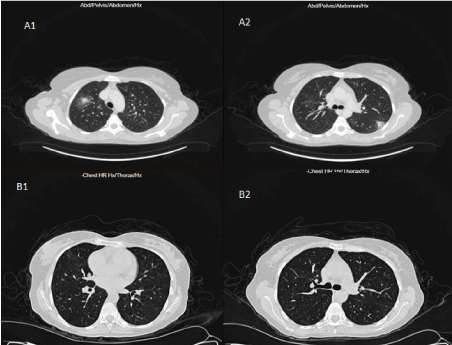

Baseline whole body computed tomography (CT) showed bilateral atypical cavitary lung lesions suggestive of invasive fungal infection (Figure 2A). The patient was empirically started on voriconazole. Ten days later, the patient showed clinical and radiological improvement (Figure 2B). Since literature data suggest ALL-oriented treatment for MPAL patients [3,4], a pre-phase therapy with steroid was administered for a week. However, minimal response on peripheral blast count was appreciated. Considering the failed response to steroid therapy, an additional negative prognostic indicator, the patient was switched to an AML-based protocol, consisting of idarubicin 12 mg/m2 for 3 days associated with cytarabine 100mg/m2 continuous infusion on days 1-7 and etoposide 100 mg/m2 on days 1-5. Bone morrow aspiration and biopsy performed at day 35 showed complete remission (CR) (blast cell<5%).

Figure 2. The high-resolution chest CT scan showed bilateral cavitary lesions (A1, A2), invasive fungal infection, and the radiological improvement (B1, B2) after treatment with voriconazole.